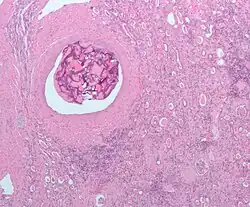

Macroscopisch onderzoek (onderzoek met het blote oog) toont een gelige, multilobulaire (meerlobbige) tumor in de nierschors met vaak zones met necrose (afgestorven weefsel), bloeding en verlittekening.

Bij licht-microscopisch onderzoek is te zien dat de tumorcellen samenklonteren tot strengen, papillen, buisstructuren of nestjes. De individuele cellen zijn atypisch (afwijkend van de normale structuur van de niercel), polygonaal (veelhoekig) en groot. Omdat de cellen glycogeen en lipiden opslaan in het cytoplasma zien ze er helder (Engels: clear), vetbeladen uit; de celkern blijft centraal in de cel, de celmembraan is duidelijk zichtbaar. Sommige cellen zien er kleiner uit met eosinofiel cytoplasma en lijken op normale tubuluscellen. Het stroma, het omringende bindweefsel van het gezwel, is verminderd, maar wel gevacuoliseerd (met vacuolen). De tumor drukt op het omringende parenchym van de nier en vormt een pseudokapsel.[24]